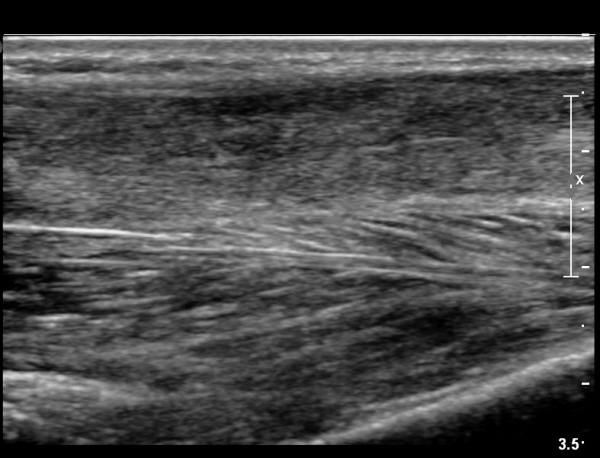

¾ÆÅ³·¹½º°Ç Àú¿¡ÄÚºÎÁ¾ÀÌ °¨¼ÒµÇ°í  ÆÄ¿­ºÎÀ§ Àú¿¡ÄÚ°¡ È£ÀüµÇ¾î

°ÇÀÇ ¼¶À¯¼º¾ç»ó(fibrillar pattern)ÀÌ È¸º¹µÇ°í ±¹¼ÒÀû ¿¬°á¼º ¼Ò½ÇÀÌ »ç¶óÁü(»çÁø 9, 10, 11, 12).